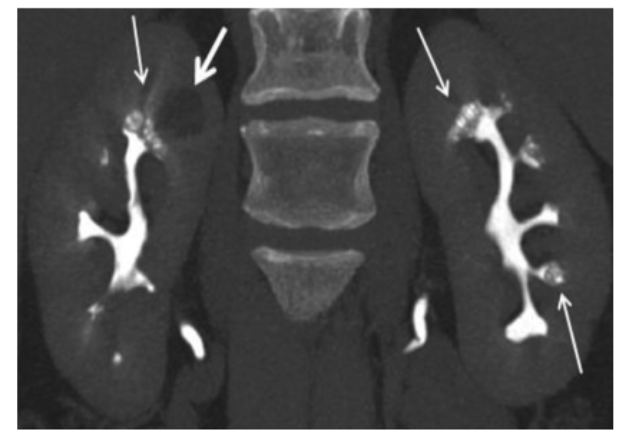

图4 MSK结石的增强CT排泄期相,可见囊状扩张的集合管被造影剂填充后出现“灯刷样"或"花束样"改变。

图5 MSK结石的增强CT三维重建,可见囊状扩张的集合管出现标志性的"花簇状"的景观。